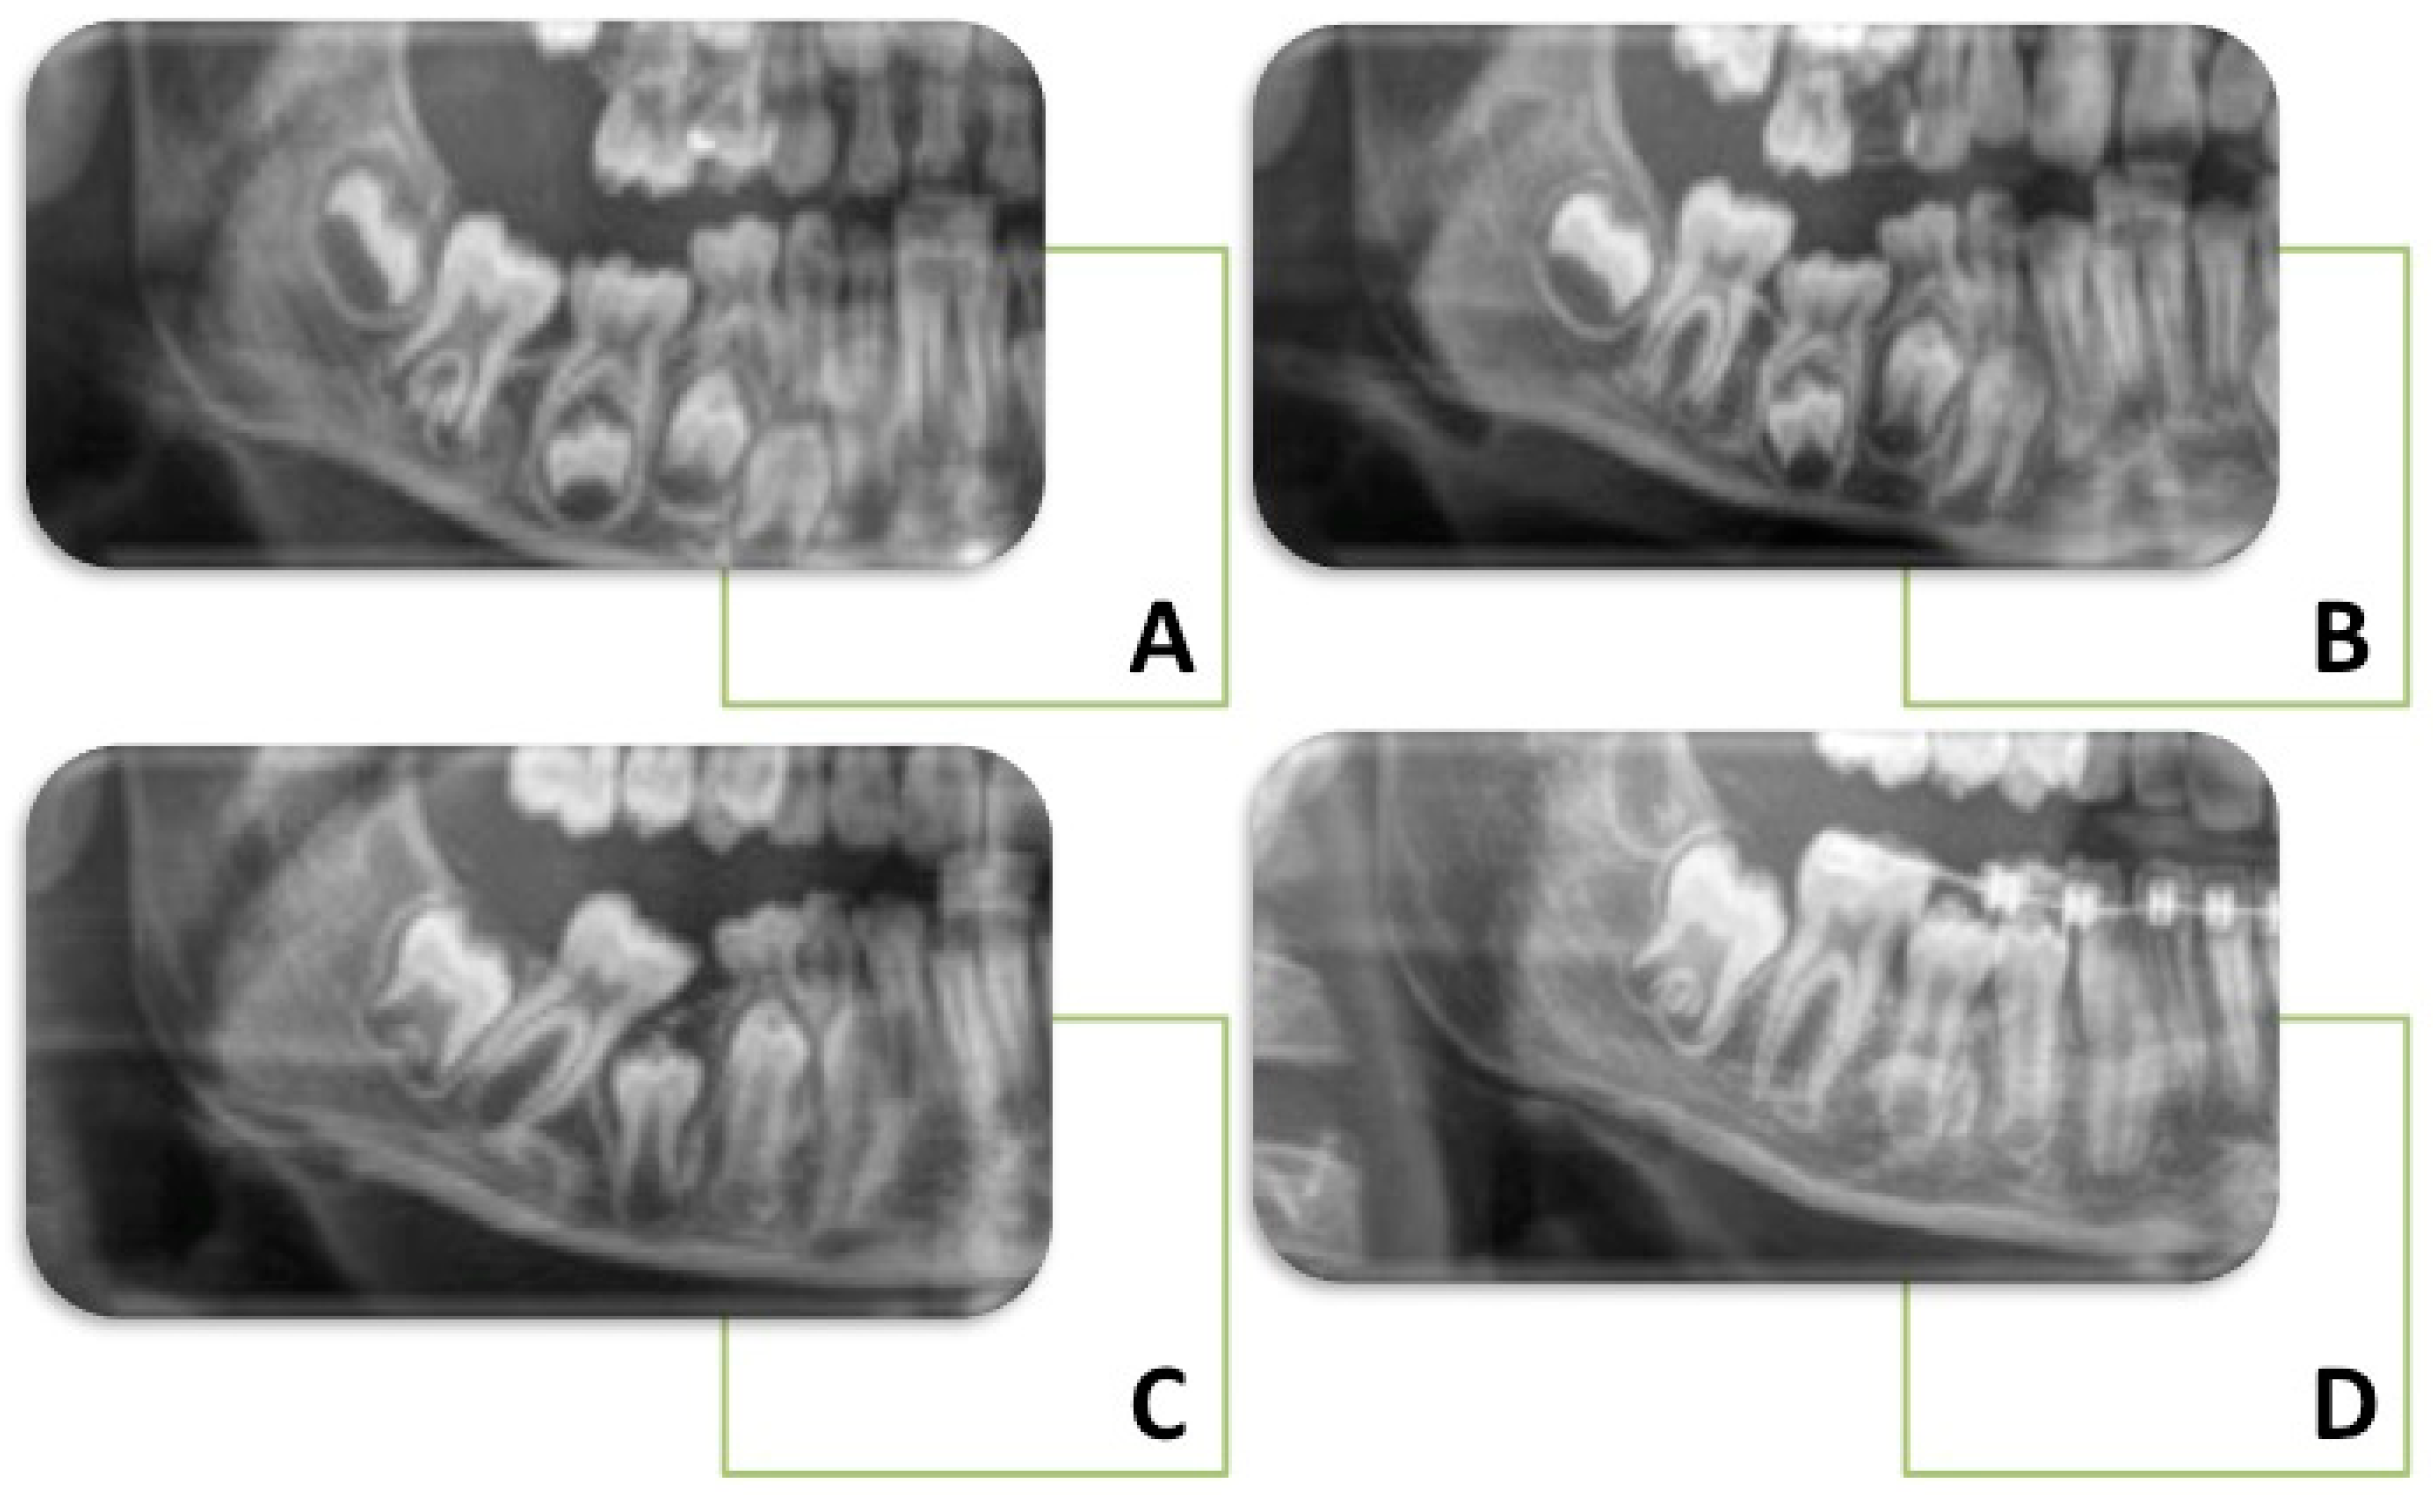

1.2. Clinical Features and Diagnosis

- Eşian, D.; Bica, C.I.; Stoica, O.E.; Dako, T.; Vlasa, A.; Bud, E.S.; Salcudean, D.; Beresescu, L. Prevalence and Manifestations of Dental Ankylosis in Primary Molars Using Panoramic X-Rays: A Cross-Sectional Study. Children 2022, 9, 1188. [Google Scholar] [CrossRef]